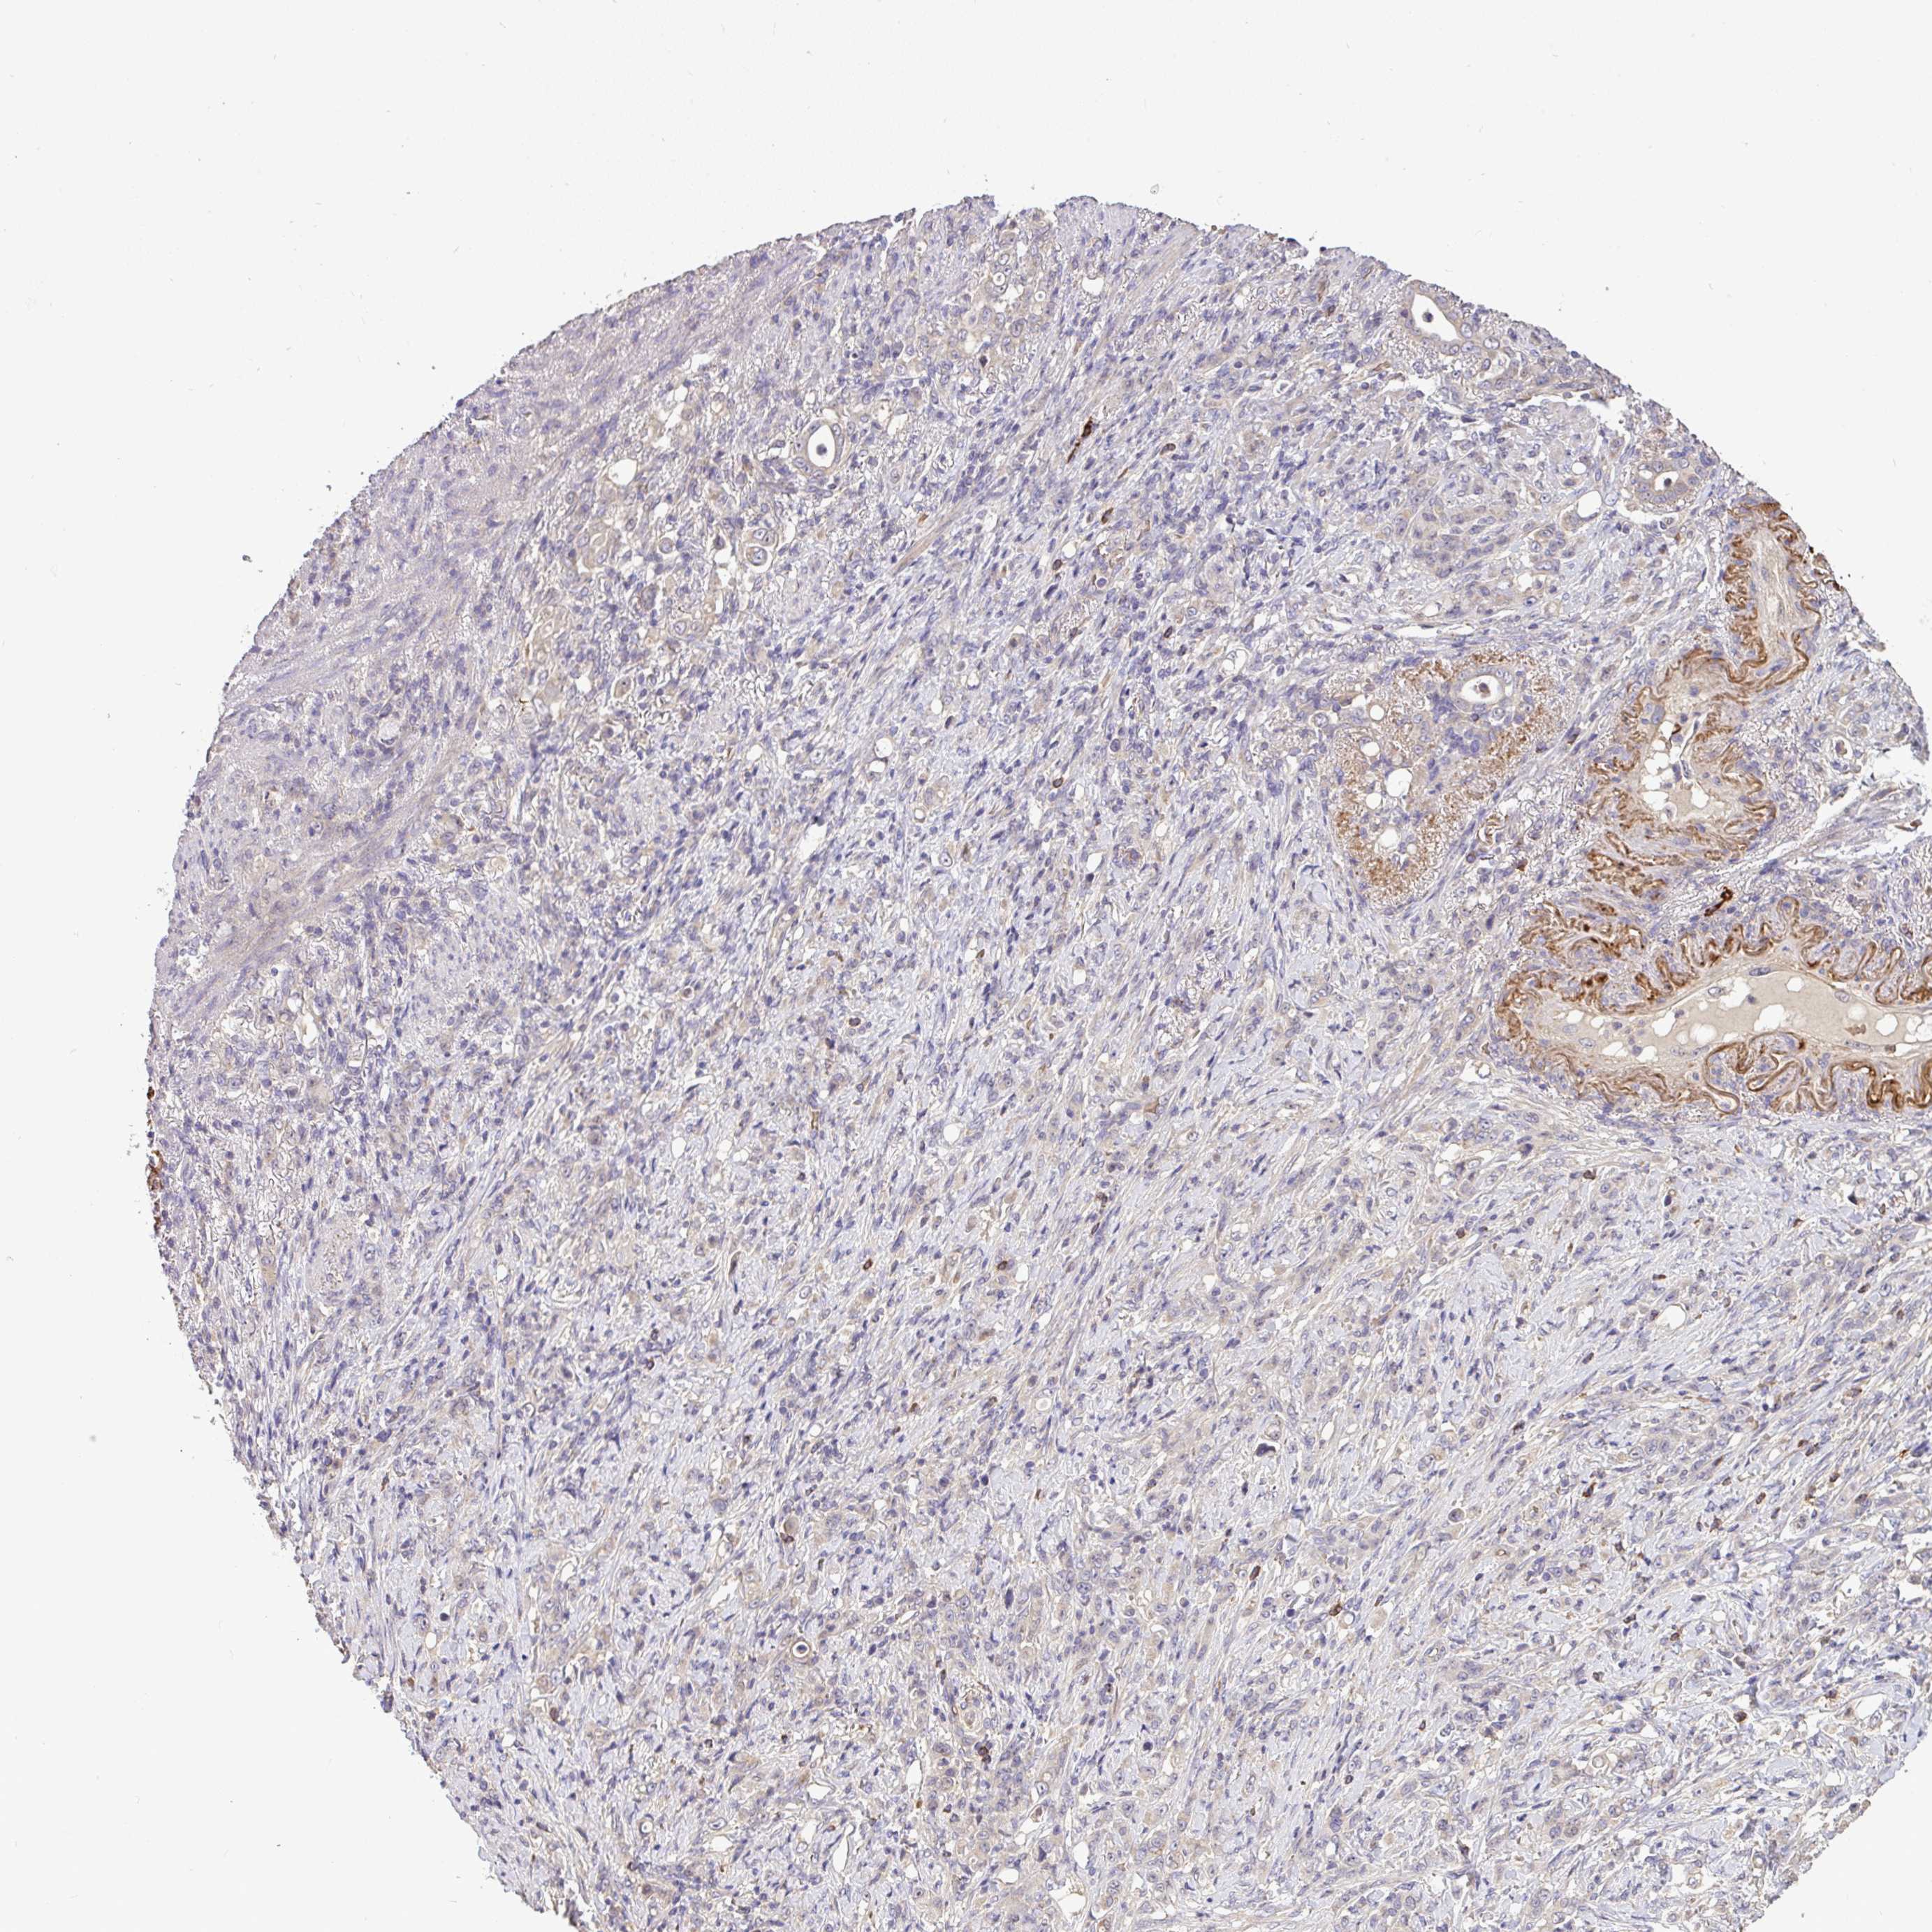

STOMACH CANCER - Protein expressioni

A mouse-over function shows sample information and annotation data. Click on an image to view it in a full screen mode. Samples can be filtered based on level of antibody staining by selecting one or several of the following categories: high, medium, low and not detected. The assay and annotation is described here.

Antibody stainingi

Antibody staining in the annotated cell types in the current human tissue is reported as not detected, low, medium, or high, based on conventional immunohistochemistry profiling in selected tissues. This score is based on the combination of the staining intensity and fraction of stained cells.

Each image is clickable and will lead to virtual microscopy that enables deeper exploration of all samples and also displays staining intensity scores, fraction scores and subcellular localization as well as patient and tissue information for each sample.

Antibody HPA056632

Staining

High

Medium

Low

Not detected

Intensity

Strong

Moderate

Weak

Negative

Quantity

>75%

75%-25%

<25%

None

Location

Nuclear

Cytoplasmic/membranous

Cytoplasmic/membranous,nuclear

Adenocarcinoma, NOS